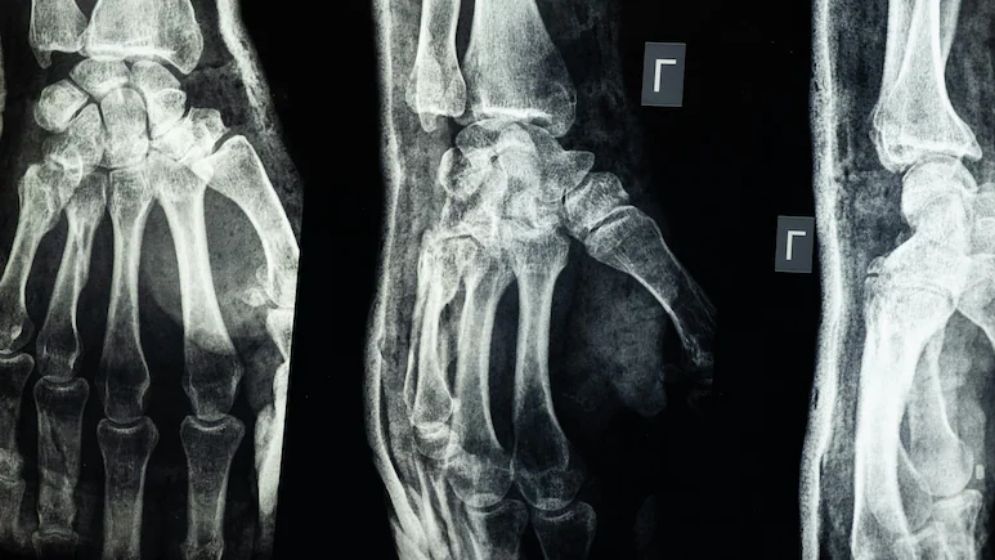

৩ মিনিটে জোড়া লাগবে ভাঙ্গা হাড়,চীনে বিজ্ঞানীদের অবিশ্বাস্য আবিষ্কার

চীনের গবেষকরা দাবি করেছেন, তারা এমন এক ধরনের চিকিৎসা আঠা তৈরি করেছেন যা মাত্র তিন মিনিটেই ভাঙা হাড় জোড়া লাগাতে সক্ষম। নতুন এই ‘বোন গ্লু’ হাড় জোড়ার পাশাপাশি ভাঙা টুকরোগুলোও স্থির রাখতে পারবে এবং হাড় সেরে ওঠার পর এটি শরীরের ভেতর থেকেই স্বাভাবিকভাবে শোষিত হয়ে যাবে। ফলে ইমপ্লান্ট অপসারণের জন্য আরেকটি অস্ত্রোপচারের দরকার পড়বে না।

বোন–০২’ নামের এই আঠার উদ্ভাবন করেছেন পূর্ব চীনের ঝেজিয়াং প্রদেশের একদল গবেষক। দলটির নেতৃত্বে আছেন স্যার রান রান শ’ হাসপাতালের সহযোগী প্রধান অর্থোপেডিক সার্জন লিন শিয়ানফেং। তিনি জানান, সাগরের পানির নিচে সেতুর গায়ে ঝিনুক যেভাবে শক্তভাবে লেগে থাকে, সেখান থেকেই তিনি হাড়ের আঠা তৈরির অনুপ্রেরণা পেয়েছেন।লিন শিয়ানফেং বলেন, এই আঠা রক্তমাখা পরিবেশেও সঠিকভাবে হাড়কে আটকে রাখতে পারে এবং দুই থেকে তিন মিনিটের মধ্যেই এটি কার্যকর হয়ে যায়। সিসিটিভি জানায়, ১৫০ জনের বেশি রোগীর শরীরে সফলভাবে এই আঠা ব্যবহার করা হয়েছে। পরীক্ষায় দেখা গেছে, আঠা দিয়ে জোড়া লাগানো হাড়ের সর্বোচ্চ বন্ধন শক্তি ছিল ৪০০ পাউন্ডের বেশি, শিয়ার স্ট্রেন্থ প্রায় ০.৫ এমপিএ এবং কমপ্রেসিভ স্ট্রেন্থ প্রায় ১০ এমপিএ।

বিশেষজ্ঞরা বলছেন, এই ফলাফল প্রমাণ করে যে ভবিষ্যতে ধাতব প্লেট ও স্ক্রুর মতো প্রচলিত ইমপ্লান্টকে প্রতিস্থাপন করতে পারে এই আঠা। এতে জটিলতা ও সংক্রমণের ঝুঁকিও অনেক কমে যাবে।